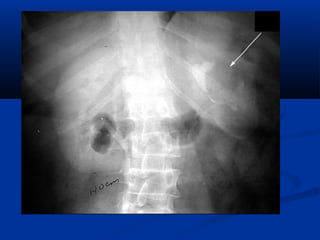

Wilms Tumor

(Nephroblastoma(

IVU:

Large soft tissue mass

distorting and displacing

the collecting system.